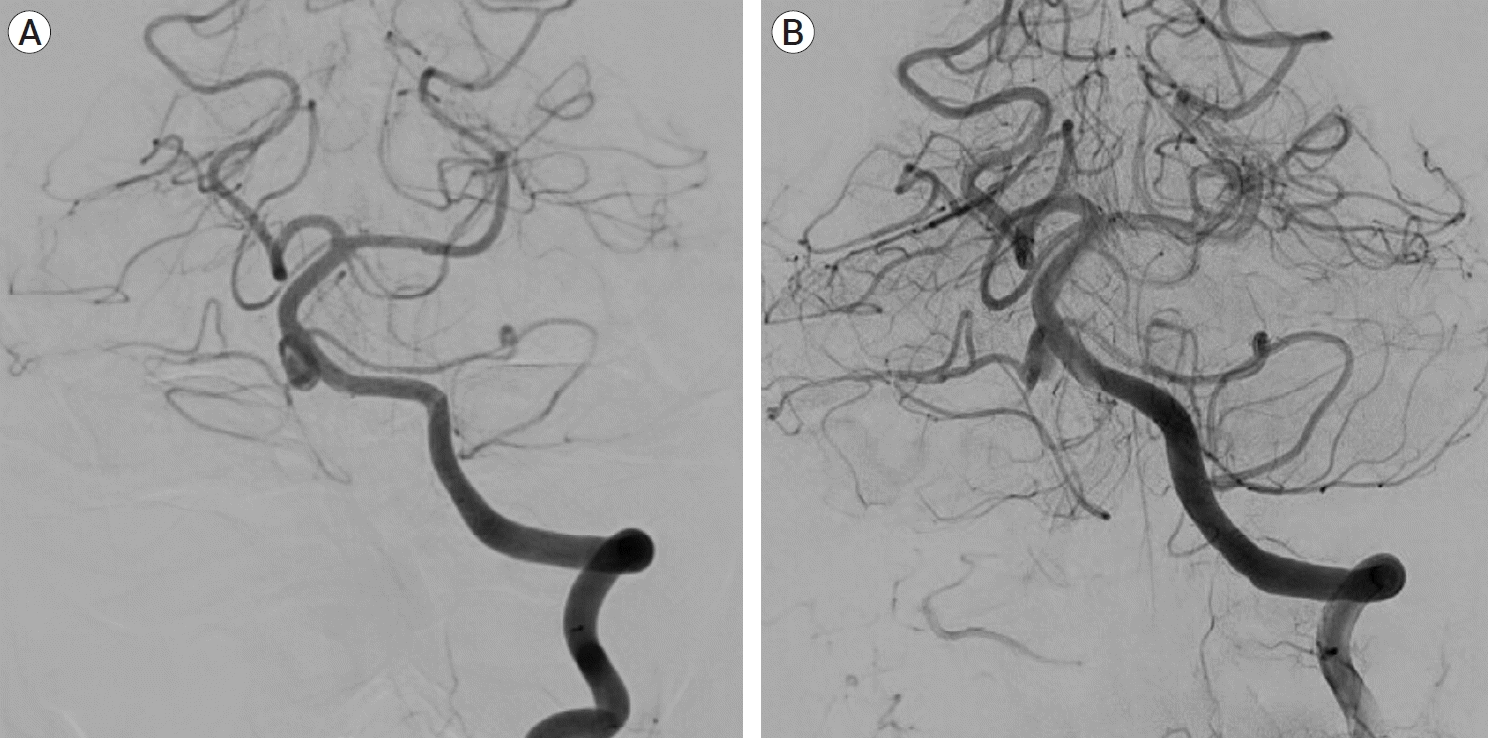

A follow-up MRI scan three months later revealed an unruptured aneurysm at the right cerebellopontine angle. A repeat head CT/CTA scan revealed the presence of an unruptured 9 mm aneurysm near the right proximal AICA, which had developed rapidly following the previous negative CTA (Fig. 2). A diagnostic cerebral angiogram was performed on the patient, which confirmed the aneurysm (Fig. 3). The scan also revealed a common AICA-PICA trunk that extended past the brainstem segment before bifurcating to supply both distal AICA and PICA territories. The left vertebral artery was dominant. The rapid growth of the aneurysm following the sudden onset of symptoms was thought to be a dissecting aneurysm with embolic phenomenon of the labyrinthine artery. The fusiform nature of the aneurysm excludes endovascular coiling in this case, but it was deemed suitable for flow diversion.

Fig. 3.

Diagnostic cerebral angiogram of the left vertebral artery, oblique view (A) and 3D reconstruction (B) showing the lack of PICA vessels bilaterally, with the AICA bifurcating and supplying both AICA and PICA territories bilaterally. There is a 9 mm fusiform aneurysm involving the proximal part of the AICA-PICA at its origin from the basilar artery. PICA, posterior inferior cerebellar artery; AICA, anterior inferior cerebellar artery